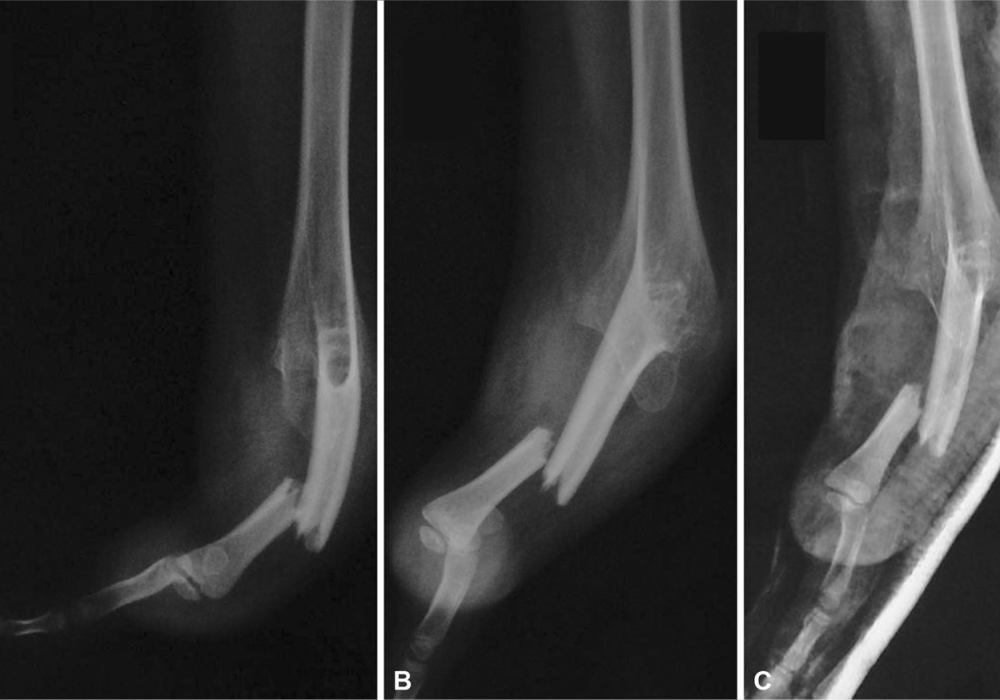

Synostosis refers to the abnormal fusion of two bones that are normally separate. In the case of the forearm, radioulnar synostosis occurs when the radius and ulna are joined by bone tissue, either partially or completely, along some portion of their length. This fusion prevents the bones from moving independently, severely limiting the rotational movement of the forearm.

• X-rays: The primary diagnostic tool, showing the extent and location of the bony fusion.